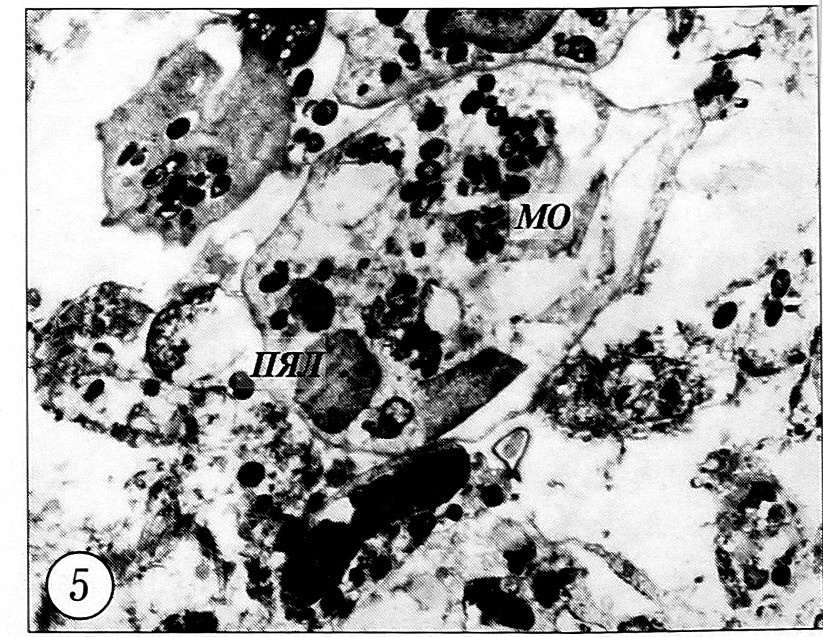

вергалась структурным изменениям, свидетельствовавшим об их лизисе. Однако при этом отмечалось разрушение многих нейтрофилов, в цитоплазме которых было сосредоточено значительное число микробных тел. Общее количество микроорганизмов, свободно располагавшихся на поверхности отломков кости и в межклеточных пространствах, значительно уменьшалось (рис. 4, 5).

Рис. 5. Фагоцитоз микроорганизмов нейтрофильными лейкоцитами, частичное разрушение их цитоплазмы. 7-е сутки после перелома, контрольная группа (ТЭМ, ув. 7500).